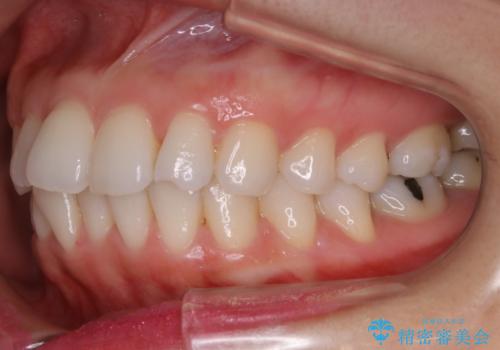

【非抜歯】前歯のガタつき マウスピースの部分矯正

- 上下の前歯の細かいガタつきの治療をご希望されて来院されました。

奥歯部分にはガタつきや噛み合わせの問題などがほとんど見られず、前歯のガタつきも軽度だったため、インビザライン ライト パッケージでの部分矯正を行うこととなりました。

今回のケースでは奥歯の噛み合わせに問題がほぼみられなかったため、前歯の位置のみに焦点を当て部分矯正を行いました。